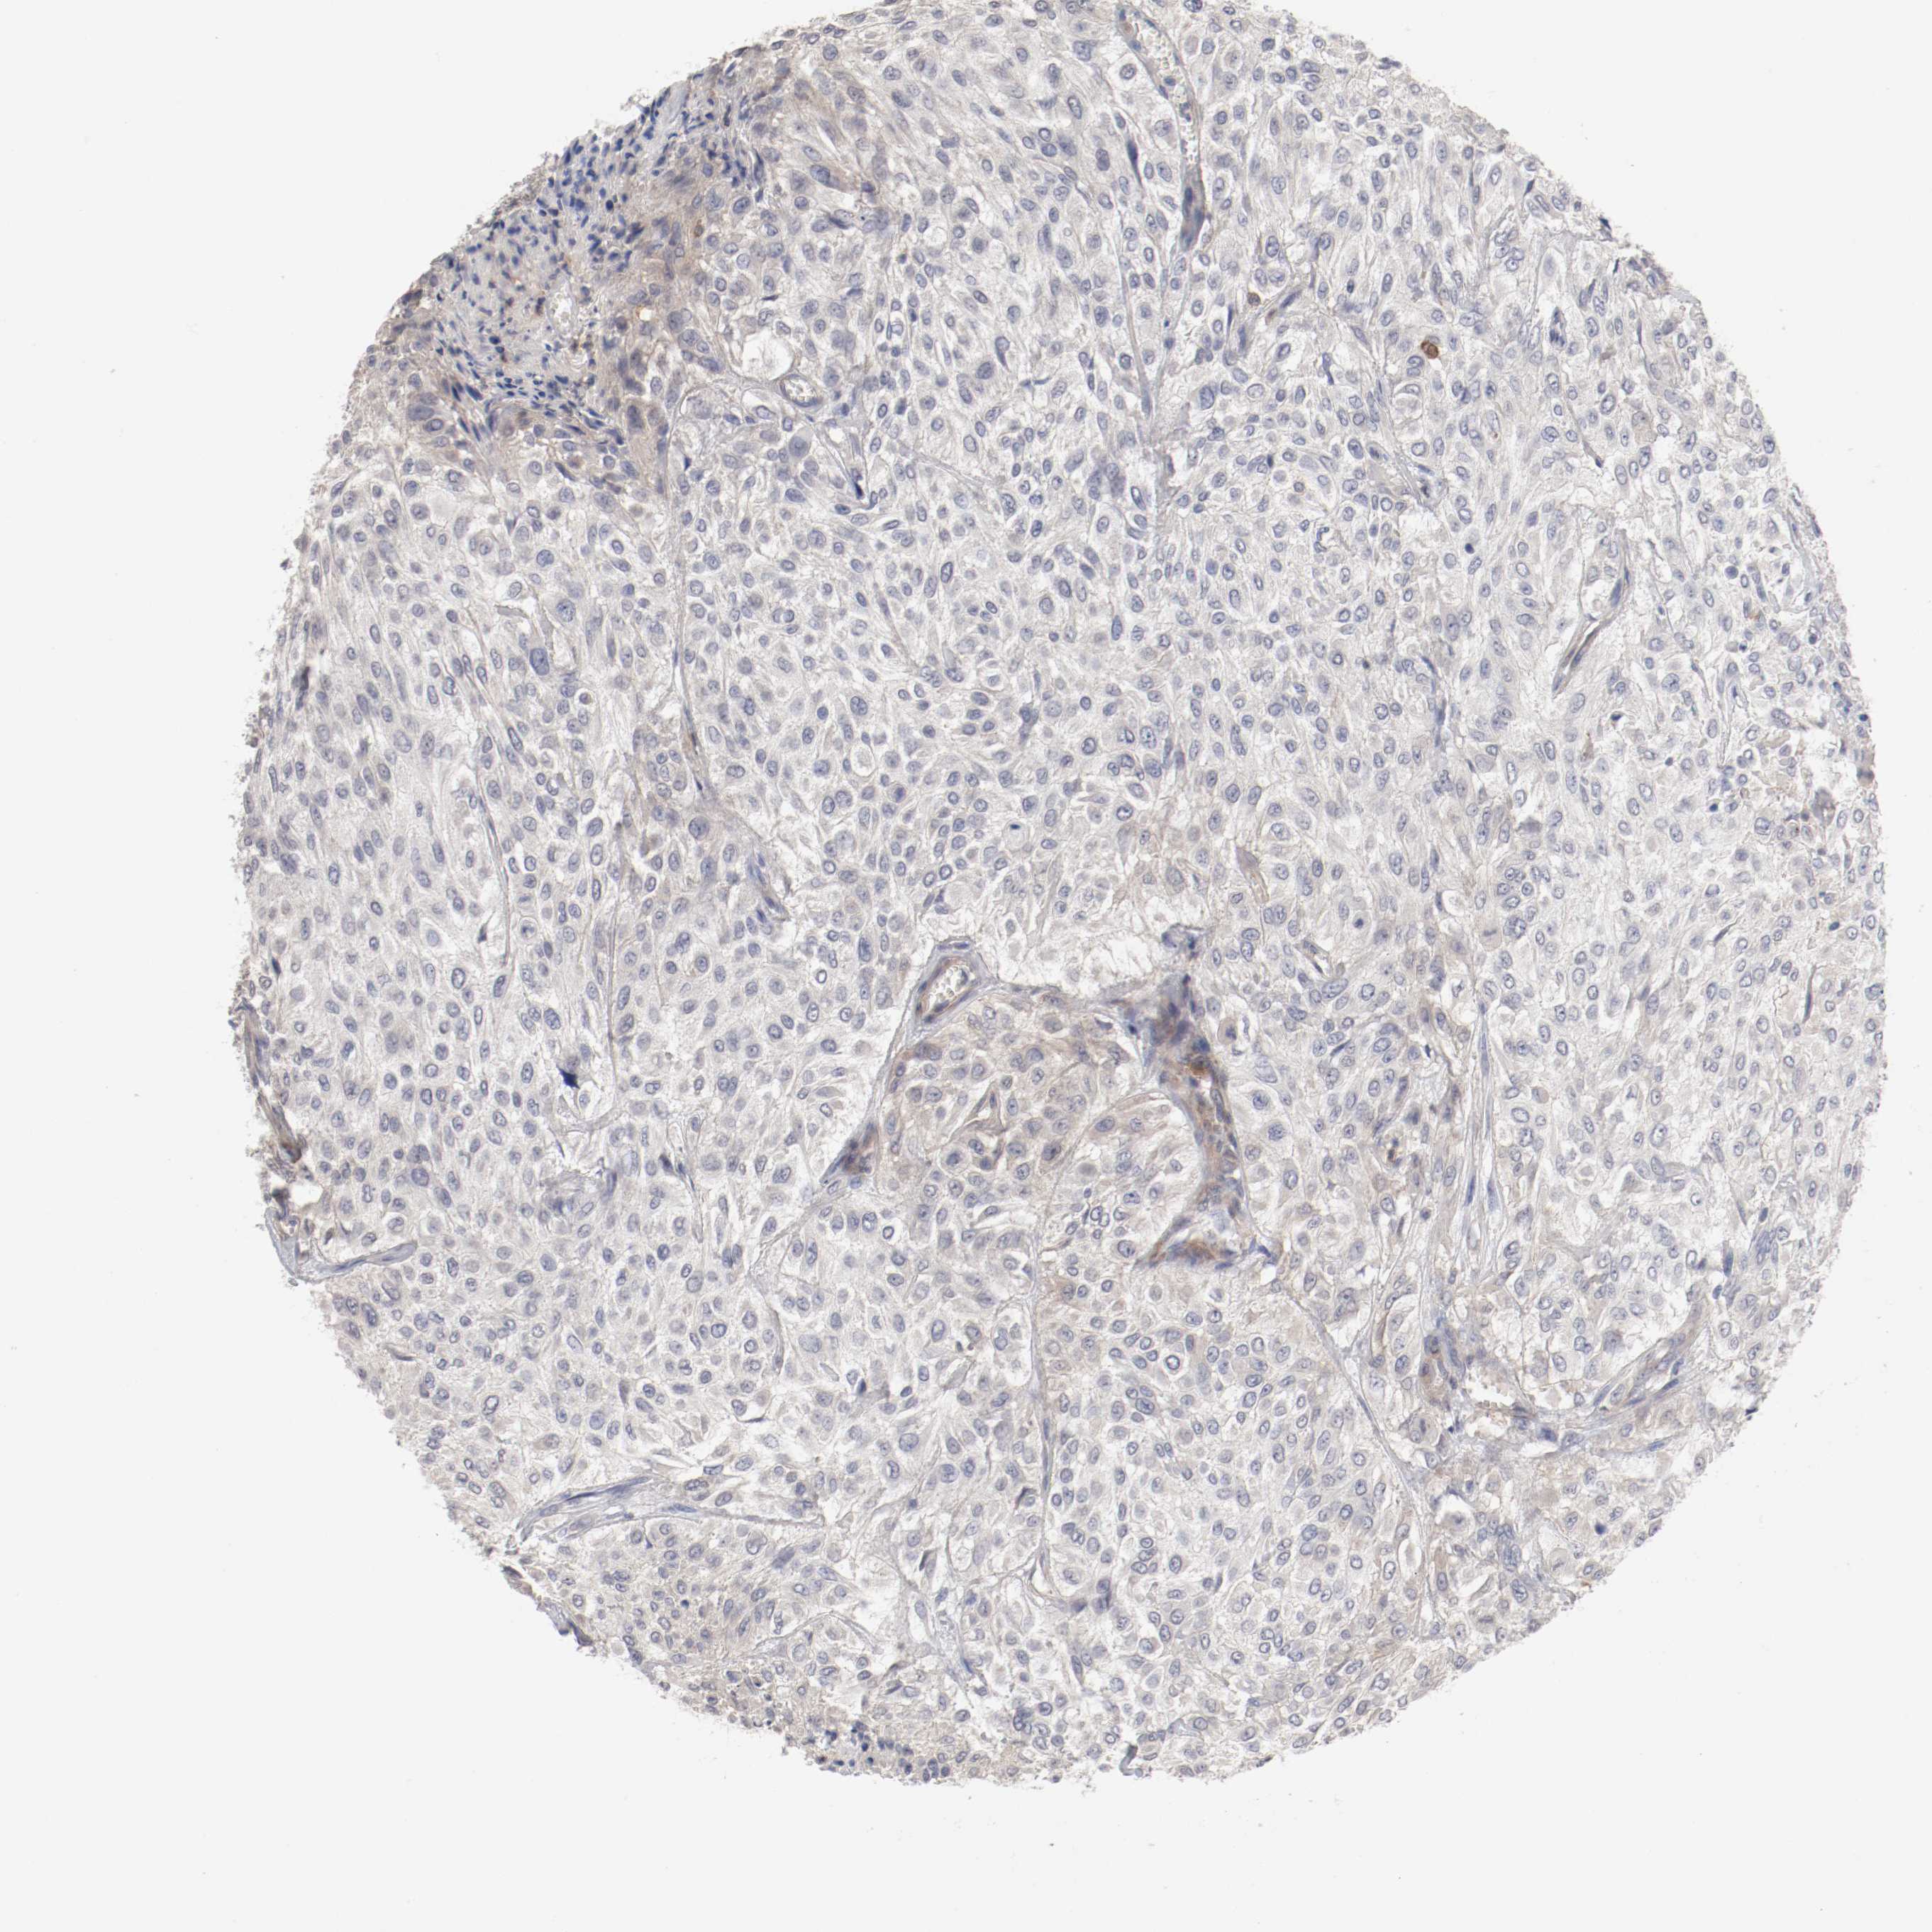

UROTHELIAL CANCER - Protein expressioni

A mouse-over function shows sample information and annotation data. Click on an image to view it in a full screen mode. Samples can be filtered based on level of antibody staining by selecting one or several of the following categories: high, medium, low and not detected. The assay and annotation is described here.

Antibody stainingi

Antibody staining in the annotated cell types in the current human tissue is reported as not detected, low, medium, or high, based on conventional immunohistochemistry profiling in selected tissues. This score is based on the combination of the staining intensity and fraction of stained cells.

Each image is clickable and will lead to virtual microscopy that enables deeper exploration of all samples and also displays staining intensity scores, fraction scores and subcellular localization as well as patient and tissue information for each sample.

Antibody HPA027956

Antibody CAB004350

Staining

High

Medium

Low

Not detected

Intensity

Strong

Moderate

Weak

Negative

Quantity

>75%

75%-25%

<25%

None

Location

Nuclear

Cytoplasmic/membranous

Cytoplasmic/membranous,nuclear

Urothelial carcinoma, Low grade

Urothelial carcinoma, High grade